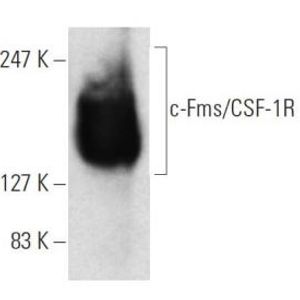

APR 19, 2024Genetics & GenomicsThere are some genes that can promote cancer; they are sometimes called oncogenes, and in tumor cells, mutations are oft ...